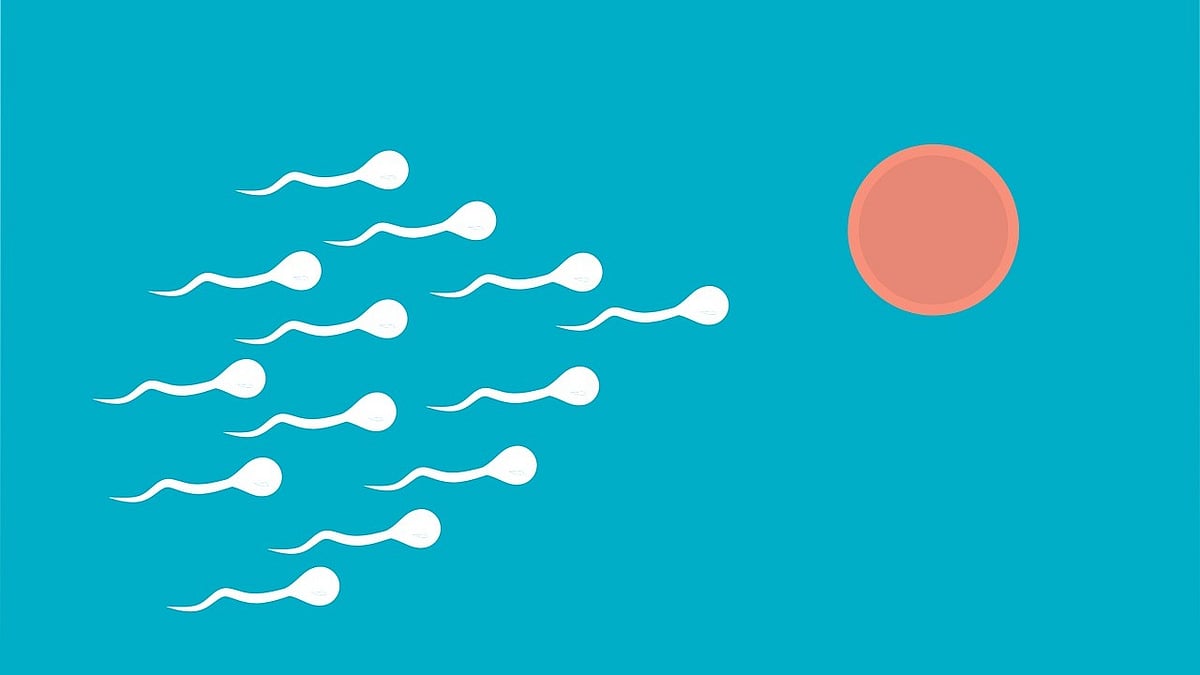

Europe: விந்தணு தானம் செய்தவருக்கு கேன்சர் மரபணு; 197 குழந்தைகளின் நிலை என்ன?

உலகம் முழுக்க குழந்தையின்மை பிரச்னை அதிகரித்து வருவதால், அதற்கான மருத்துவ சிகிச்சை முறைகளும் முன்னேறிக்கொண்டே வருகின்றன. அவற்றில் ஒன்றுதான் விந்தணு தானம்.

வெளிநாடுகளில் பரவலாக பின்பற்றப்பட்டு வரும் இந்த முறையில், விருப்பமுள்ள ஆண்கள் தங்கள் விந்தணுக்களை தானமாக வழங்குவர், குழந்தையின்மை பிரச்னை உள்ள பெண்கள், தங்களுடைய கணவருக்கு விந்தணுக்களில் பிரச்னை உள்ள பெண்கள் முகம் தெரியாத ஓர் ஆணின் விந்தணுக்களைப் பெற்று கருத்தரித்து குழந்தை பெற்றுக்கொள்வார்கள்.

இந்த மருத்துவ தகவல்கள் நம் எல்லோருக்குமே தெரிந்த விஷயம் தான். இப்போது இதைப்பற்றி பேசுவதற்கான காரணம், சமீபத்தில் ஐரோப்பாவை சேர்ந்த இளைஞர் ஒருவர், தான் கல்லூரி மாணவராக இருந்த காலத்தில் இருந்து கடந்த 17 வருடங்களாக விந்தணு தானம் செய்து வந்திருக்கிறார்.

இந்த தானம் செய்வதற்கு முன்னால் அவருடைய உடல்நலம் குறித்த அத்தனை பரிசோதனைகளிலும் அவர் ஃபிட்டாகவே இருந்திருக்கிறார்.

இந்தக் காரணத்தால்தான் அவர் தொடர்ந்து விந்தணு தானம் செய்து வந்திருக்கிறார். இந்த நிலையில், தற்போது அவருடைய உடல் செல்களில் ஒரு பிறழ்வு இருக்கிறது. இந்தப் பிறழ்வு அவருடைய TP53 என்ற மரபணுவை பாதித்திருப்பது கண்டுபிடிக்கப்பட்டுள்ளது.

சரி, இதனால் என்னவாகும் என்கிறீர்களா? இந்த மரபணுதான், நம் உடல் செல்களின் வளர்ச்சியை சரியாகக் கட்டுப்படுத்தும். இன்னும் விளக்கமாக சொல்ல வேண்டும் என்றால், செல்களின் அசாதாரண வளர்ச்சியைக் கட்டுக்குள் வைத்து நமக்கெல்லாம் புற்றுநோய் வராமல் காப்பாற்றுவது இந்த மரபணுதான்.

இந்த மரபணுவில்தான் அந்த ஆணுக்கு பிரச்னை இருந்திருக்கிறது. அதுவும் இந்த பிரச்னை அவருக்குப் பிறவியிலேயே இருந்திருக்கிறது. இது எதுவும் தெரியாமல்தான் அவர் விந்தணு தானம் செய்து வந்திருக்கிறார். இந்த மரபணு பிறழ்வை பரிசோதனைகளிலும் ஆரம்ப காலத்தில் கண்டுபிடிக்க முடியவில்லை. ஏனென்றால், இது ஓர் அரிய வகை மரபணு கோளாறு ஆகும்.

இந்த நிலையில் இரண்டு வருடங்களுக்கு முன்னால் ஐரோப்பாவில் இருக்கிற ஒரு விந்து வங்கி இந்த பிரச்னையை கண்டுபிடித்து அந்த நபரையும் அடையாளம் கண்டுவிட்டது.

இதன் பிறகு, இந்த ஆணிடம் பெற்ற விந்தணு தானம் மூலம் பிறந்த குழந்தைகளில் சிலருக்கு புற்றுநோய் வந்திருப்பது கண்டறியப்பட்டுள்ளது.

சில குழந்தைகள் புற்றுநோய் ஏற்பட்டு மரணமும் அடைந்திருக்கிறார்கள். தவிர, இவருடைய விந்தணுக்கள் மூலம் பிறந்தவர்களுக்கு அவர்களுடைய வாழ்நாளில் ஏதோ ஒருவகை புற்றுநோய் வருவதற்கு வாய்ப்பு இருக்கிறது என்பதால், பலரும் அச்சத்திலும் மன வருத்தத்திலும் இருக்கிறார்கள்.

ஐரோப்பா முழுவதிலும் குறைந்தது 197 குழந்தைகளுக்காவது இவர் தந்தையாக இருப்பார் என்பதால், விந்தணு தானம் மூலம் குழந்தைப் பெற்ற குடும்பங்கள் மன அழுத்தத்தில் இருக்கின்றன.

கவனம் மக்களே இப்படியும் ஒரு பிரச்னை இருக்கிறது!